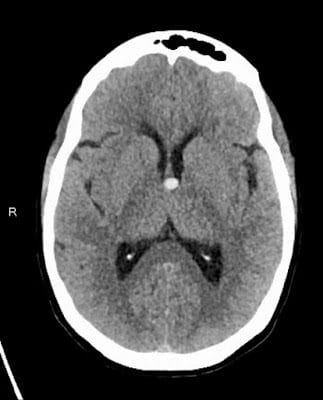

The Neuro surgeon, Dr. Christian Ramsey (who is such a great guy!), came in early Sunday morning and explained that the CT scan showed I had a Colloid Cyst (white dot in the above picture) in the third ventricle of my brain which was blocking the Cerebral Spinal fluid (CSF) from circulating causing Obstructive Hydrocephalus, which, if left untreated, could lead to death. He then explained that the best way to remove my cyst was the most risky and invasive way by making an incision in the top of my head (Craniotomy) and digging down through the Corpus Callosum, which separates both hemispheres of the Cerebrum, to reach the ventricles. Dr. Ramsey was pretty sure that my cyst was more solid, and therefore could not be performed endoscopically. He also explained that I was moved to the N-ICU (Neurology ICU) where I could be monitored pre and post-operative every hour due to my hydrocephalus and increased seizure risk, both of which were also being treated with IV medications. Even though Colloid Cyst are rare, Dr. Ramsey assured us that he was the right person for the job due to the fact he did a fellowship in Finland with the top Colloid Cyst specialist in the world, and he even wrote a paper on Colloid Cysts (tender mercy)! He ended up talking with us for a good forty-five minuets, but we still felt like we should get a second opinion or something, after all, this was brain surgery. So Brad had a long talk with our family physician, whom we really like and trust, and felt better about the whole thing, especially after finding out the two were good friends, and that Dr. Ramsey had already spoken with our family physician. Brad also asked our nurses what they thought of Dr. Ramsey and they all agreed that he was a very smart, dedicated and thorough doctor who really cared for his patients.

The surgery was a success, and the above picture is of my CT scan the afternoon after surgery. The cyst is gone and there is good flow of CSF through the ventricles. They also closed my skull with titanium plates and screws which the doctor assured me would not go off at the airport.